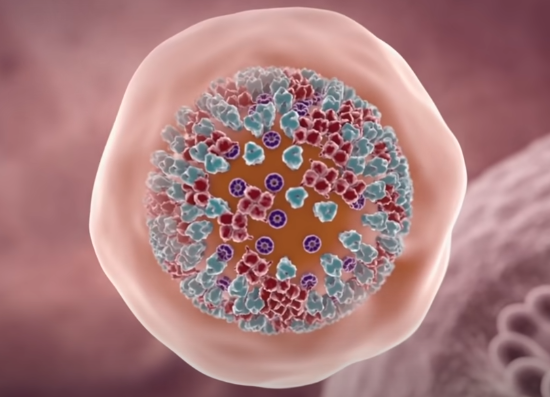

这里,病毒为了安全会开启自己的易容术技能,也就是在外面包裹一层细胞膜,进而潜入细胞深处。利用这层伪装,病毒可以轻松的在细胞工厂内部游荡。

直到遇到合适的时机,它会脱去包膜,释放体内的 RNA。这里的 RNA 身兼两项任务,一是合成病毒蛋白质组件,二是复制 RNA 自身。